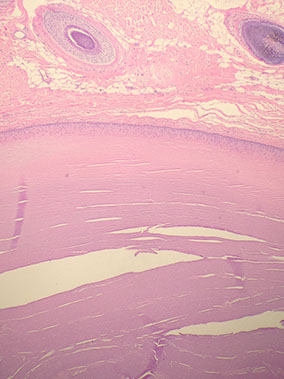

Trichilemmal (pilar) cyst

2nd MCC epidermal cyst (after inclusion), mostly on scalp of women

- may have AD inheritance

Histo: lined by stratified squamous epithelium w/o inner granular layer and abrupt keratinization (like the trichilemma of the outer root sheath of a hair follicle)

- made of hard keratinaceous material that can have calcifications